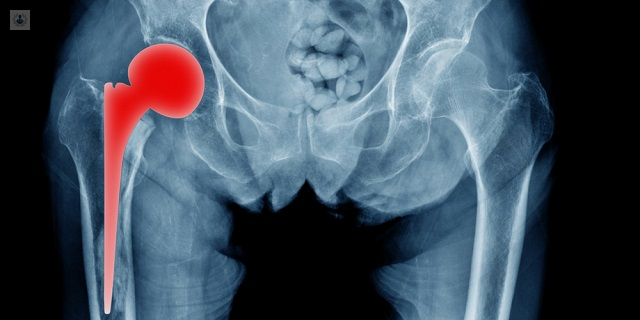

¿Qué es la Prótesis Dolorosa?

Las Prótesis Dolorosas son aquellas que se presentan con un dolor anormal luego del periodo de recuperación, estas son principalmente de la rodilla, ya que es una articulación más susceptible a desgastarse. El periodo de recuperación depende del propio paciente, las cirugías que se le realizaron, el tipo de prótesis, entre otras.